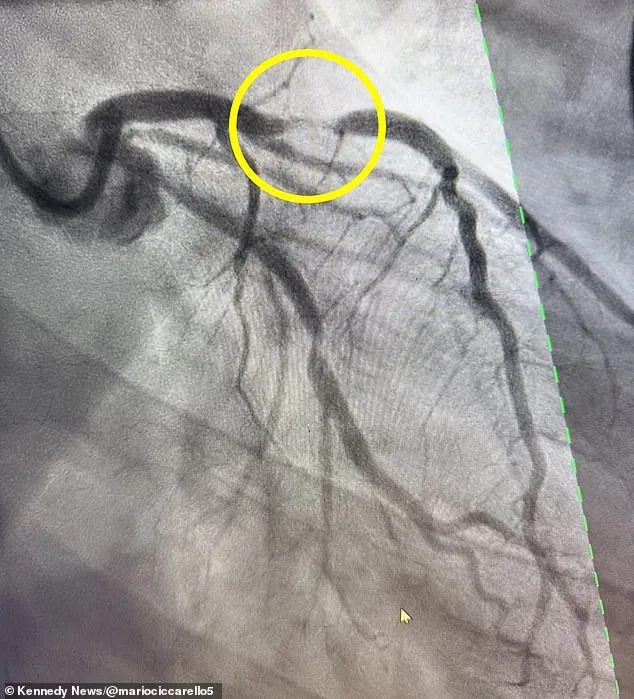

Doctors discovered that Ciccarello had suffered a 95 percent blockage in his left anterior descending (LAD) artery, which supplies more than half of the heart's blood. This type of blockage is associated with a 'widow-maker' heart attack, a term that refers to the high mortality rate linked to this condition. Doctors estimate that only 12 percent of patients survive this type of event, as the immediate damage to the heart's pumping chamber is often catastrophic.

Widow-maker heart attacks are more common in men, especially in their 40s, though women over 50 can also be at an increased risk. Pictured is a scan showing the blocked LAD artery in Ciccarello's heart, a clear visual representation of the life-threatening condition he faced.